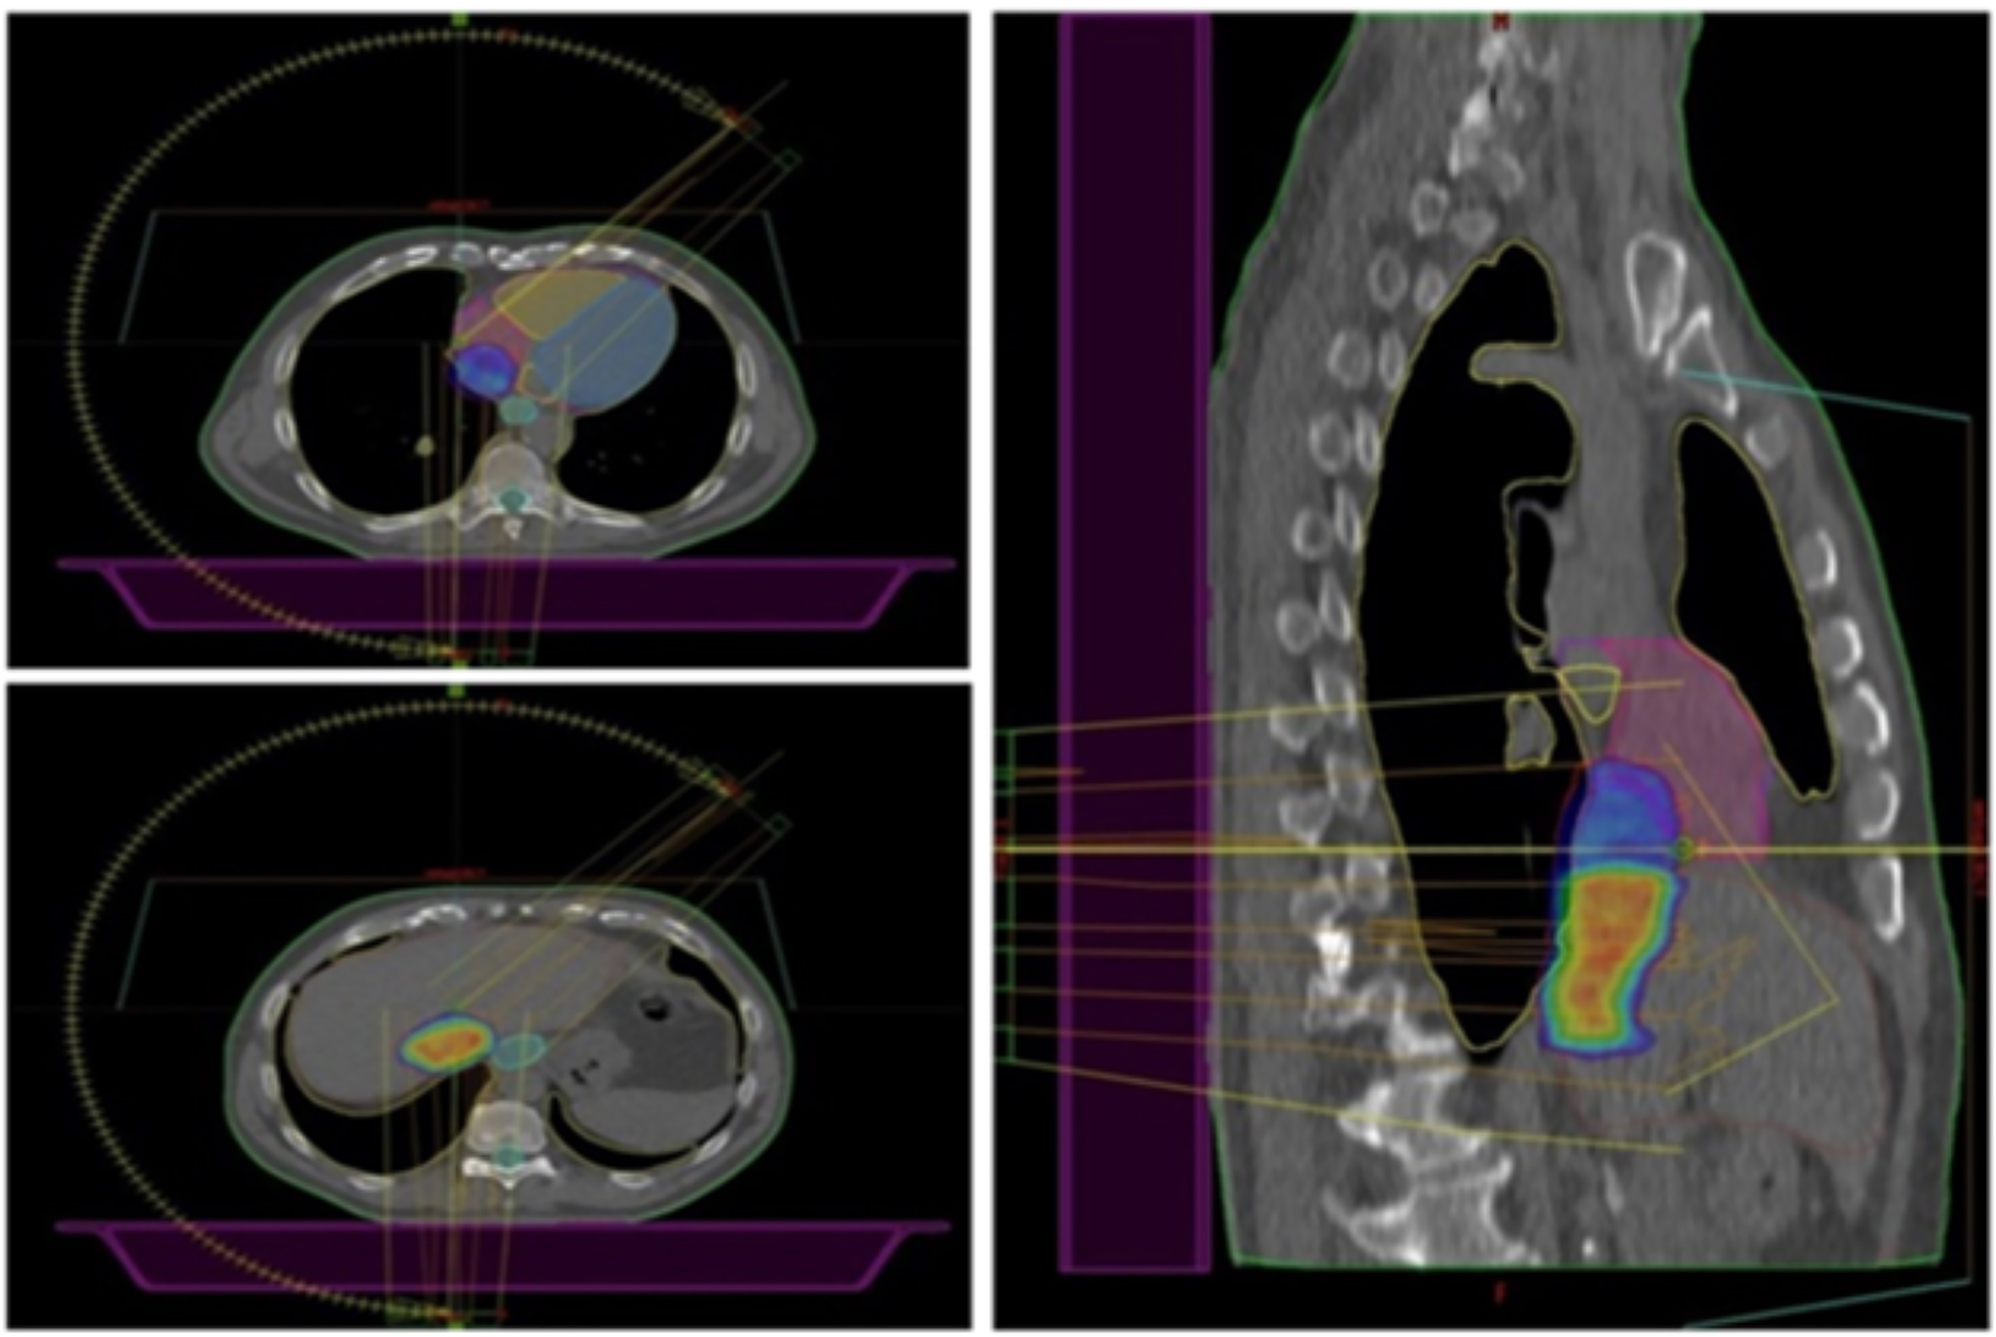

After weighing the pros and cons, we decided to perform stereotactic radiotherapy via a Novalis Truebeam STx (Varian, Palo Alto, CA, USA). CT simulation was performed using a “slow” four-dimensional (4D) computed tomography (4D-CT) capturing any target motion during the respiratory cycle with a slice thickness of 1.25 mm. Once the most stable individual respiratory phases were selected, the IVC-TT was delineated as gross tumor volume (GTV) on the CT simulation, which was also merged with the diagnostic contrast-enhanced CT scan aiming for a more precise delineation of the target. To compensate for target motion and ensure target coverage, considering the non-negligible intra-fraction target displacement observed during CT simulation due to heartbeats, the planning target volume (PTV) was generated by adding 5 mm of isometric margins to the GTV. The tumor location concerned us about possible radiation-related cardiac toxicity. To reduce the dose received by the heart, two prescription levels were chosen: a dose of 32.5 Gy in five daily fractions had to include the entire TT, including its tract abutting and invading the right atrium, while a simultaneous integrated boost (SIB) up to 40 Gy was planned to target the intrahepatic tract exclusively (Figure 1). The treatment was delivered with a Varian Truebeam linear accelerator (Varian Medical Systems, Palo Alto, CA, USA) using 10 MV Flattening Filter Free (FFF) photon beams for faster delivery.

Axial (on the left) and sagittal (on the right) planes showing the 98 % dose distribution. Two prescription dose levels are depicted: the hotter yellowish/reddish dose color-wash refers to the highest dose prescription (40 Gy to the SIB volume), which gradually fades into the colder bluish lower dose (32.5 Gy) to the longitudinal section of the TT closer to the heart to reduce the risk of cardiac toxicity.